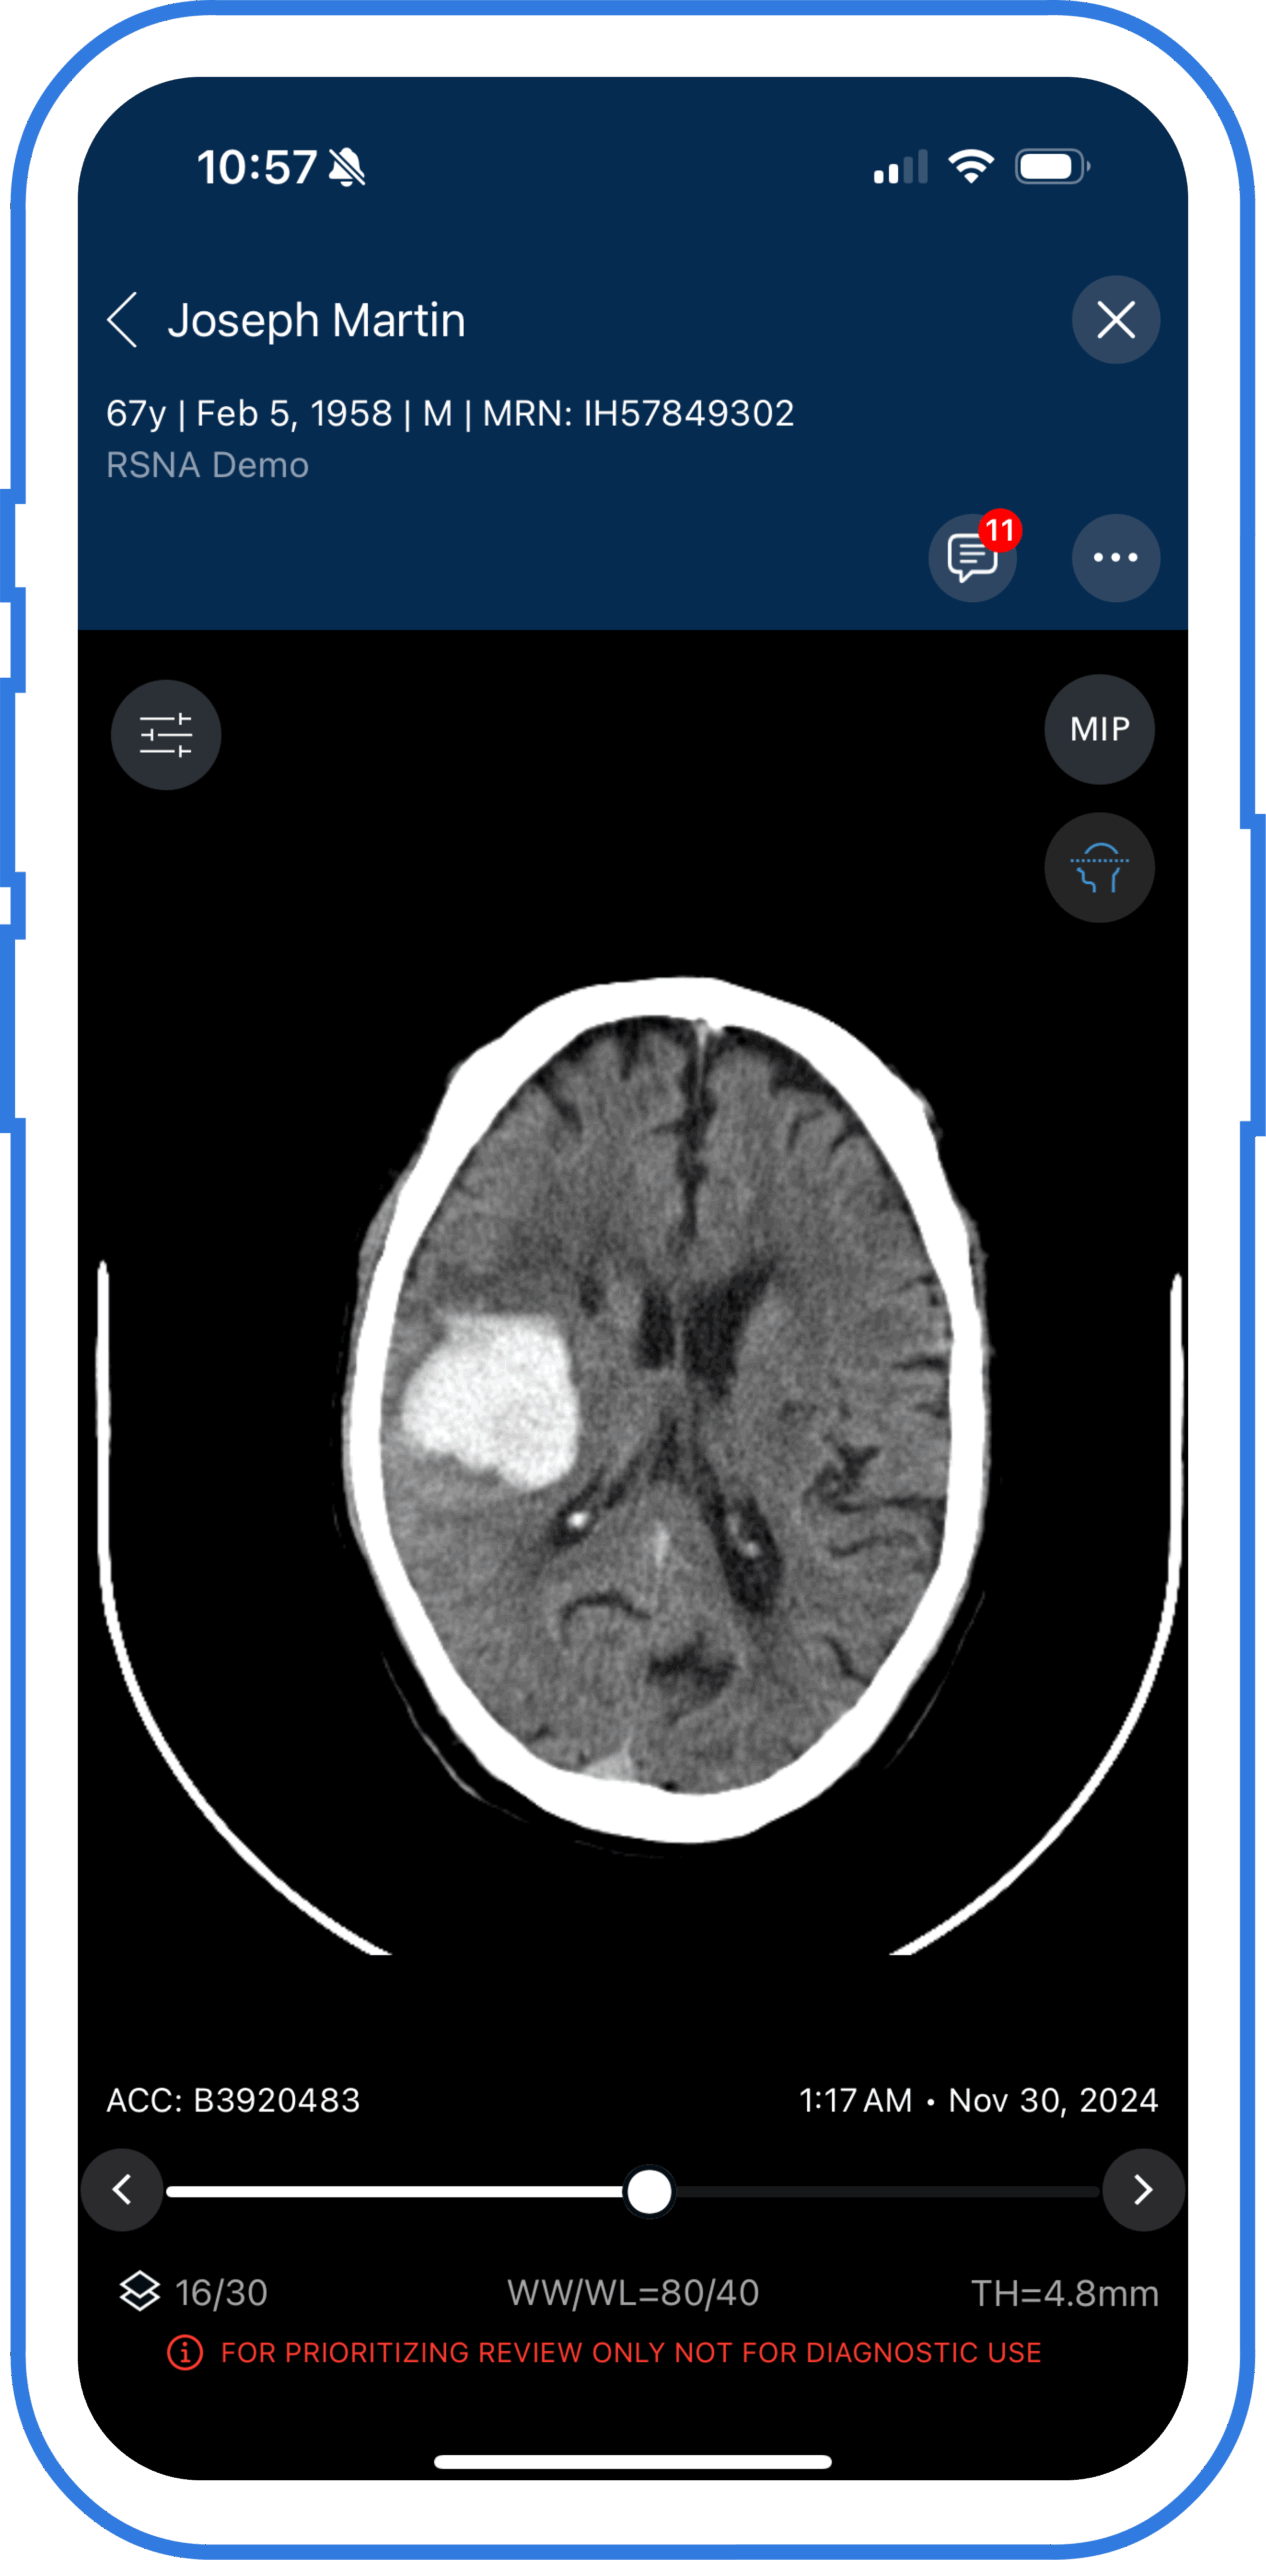

Intracerebral hemorrhage (ICH) scan

Automatic AI detection of suspected acute and chronic hemorrhage down to 1 ml.

Real-time ICH detection and quantification

Consistent, accurate measurements available on desktop and mobile device for decision making on-the-go.

Viz Hemorrhage harnesses the power of AI to provide precise and reliable detection and quantification of intracerebral hemorrhages. Accurate volume measurements of brain bleeds are crucial for assessing the severity of cases, monitoring progression, and planning treatment strategies.

The study highlights how Viz ICH and Viz ICH Plus promptly identified a right parieto-occipital hematoma in a patient presenting with a headache, resulting in a marked reduction in interhospital transfer (IHT) time.